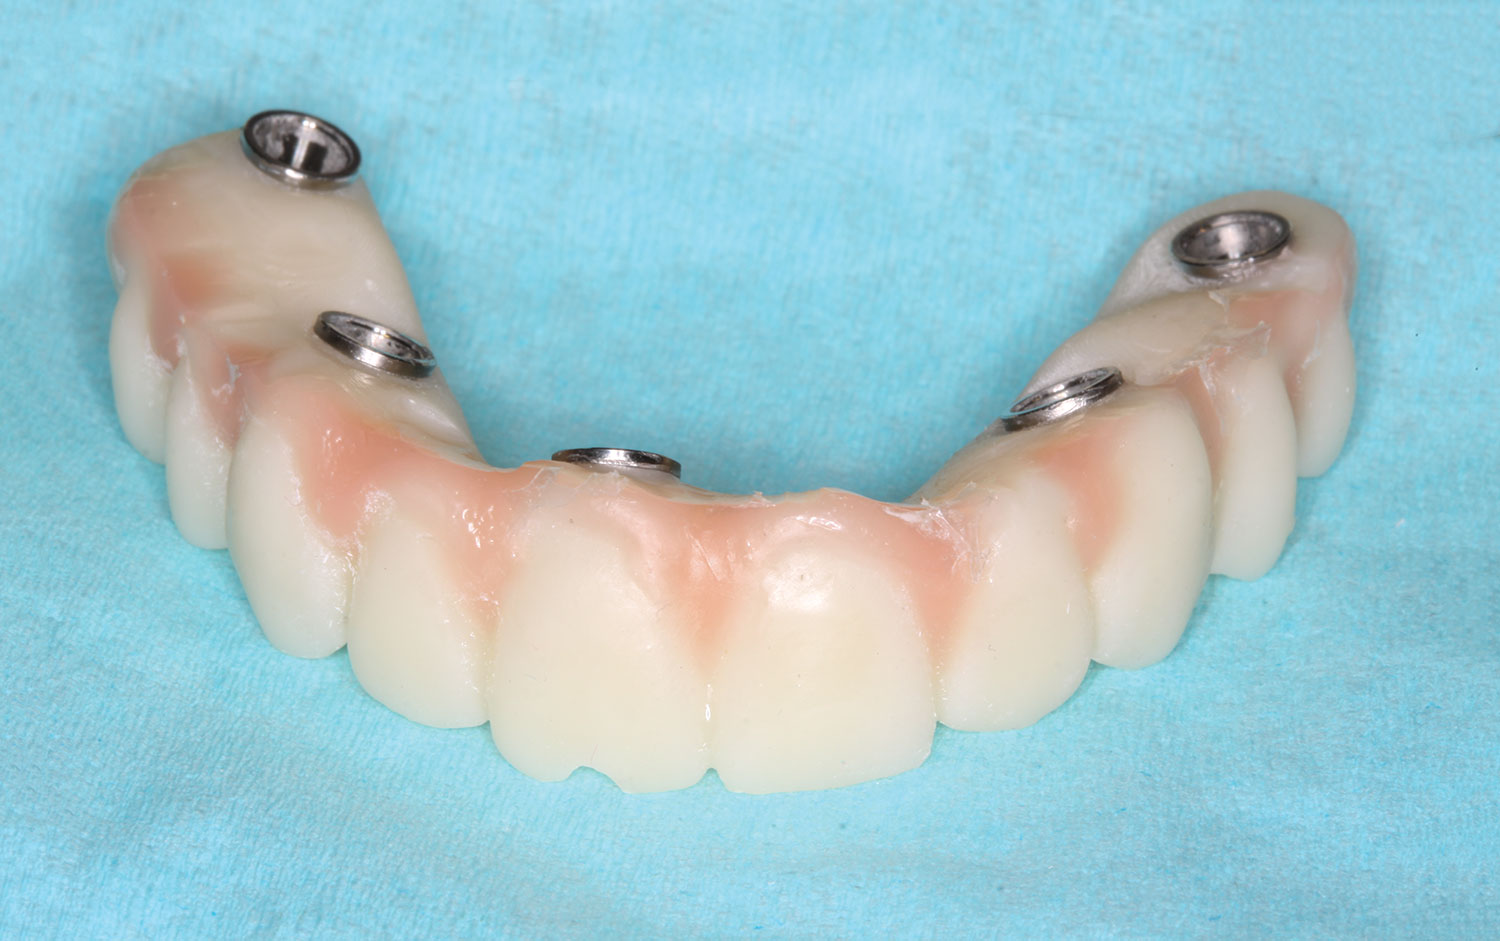

The implant company then returned an STL design file electronically via email. The office staff sent this file to the practice's 3D printer, and the appropriate color nanoceramic resin was used to print the prosthesis at 100 microns. Next, metal titanium (ti)-base cylinders, made specifically for the multi-unit abutments, were inserted into the prosthesis, which was then stained and glazed, and gingival color was applied to establish optimum esthetics (Figure 5).

Several hours later the dental team received the STL file, from which they would print the maxillary prosthesis on a 3D printer using appropriately colored nanoceramic resin. The prosthesis was stained and glazed, and metal cylinders were inserted into the undersurfaces

of the screw-access holes, each of which was specifically located to fit on the multi-unit abutments (Figure 16 and Figure 17).

This file was then electronically returned to the dental team via the proprietary web portal. The office staff then sent the STL design file to the practice's 3D printer software, and the appropriate color nanoceramic resin was used to print the prosthesis at 100 microns. Once this was accomplished, the prosthesis was stained and glazed and gingival color was applied to establish optimum esthetics.

The completed prosthesis was then screwed directly onto the multi-unit abutments with Rosen screws with no ti-bases and torqued to 20 Ncm. Screw-access holes were filled, and no occlusal adjustment was necessary. The fit of the prosthesis was precise and stable and the phonetics of the patient was ideal. The patient was overwhelmed by the significant esthetic improvement with this set of teeth in place.